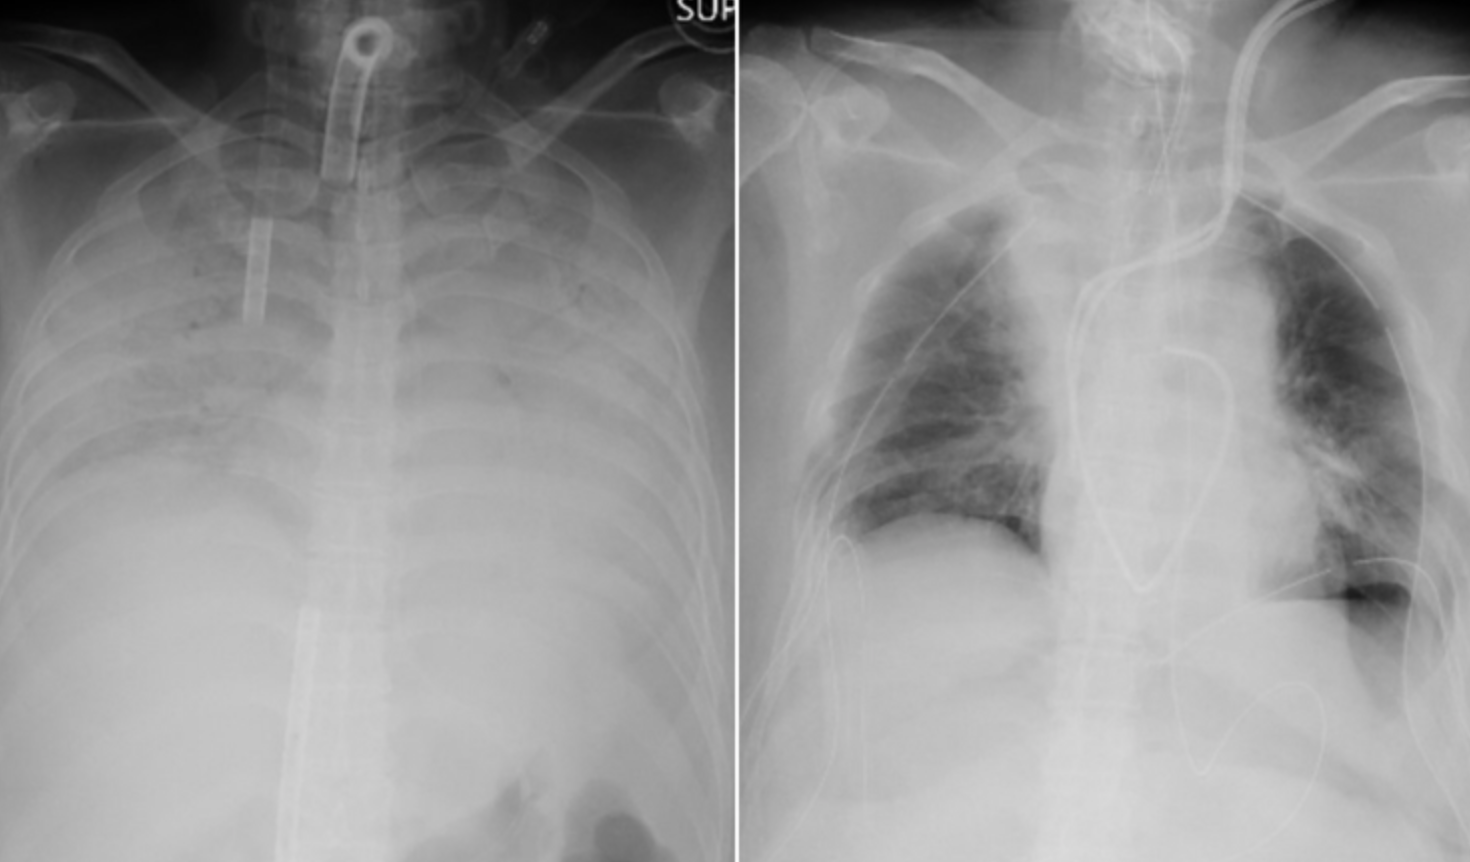

Un estudio publicado a principios de este año de más de 1.700 pacientes tratados en la ciudad china de Wuhan, zona cero de la pandemia, encontró que las radiografías de pacientes gravemente enfermos mostraron evidencia de daño pulmonar meses después de su infección.